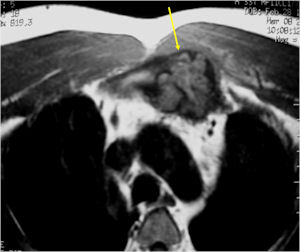

MRI:

- Also useful in determining extent

- There is often extensive edema around the tumor in the surrounding bone and soft tissues that can lead to a misdiagnosis of a malignant tumor.

- There may be expansion of bone, cortical thinning and cortical breakthrough. A soft tissue mass may accompany this lesion but the soft tissue component is usually contained by the periosteum.

- The periosteum remains intact around the soft tissue component. Might need a CT scan to detect the subtle calcification (Egg Shell Rim of Calcification) associated with an intact periosteal reaction